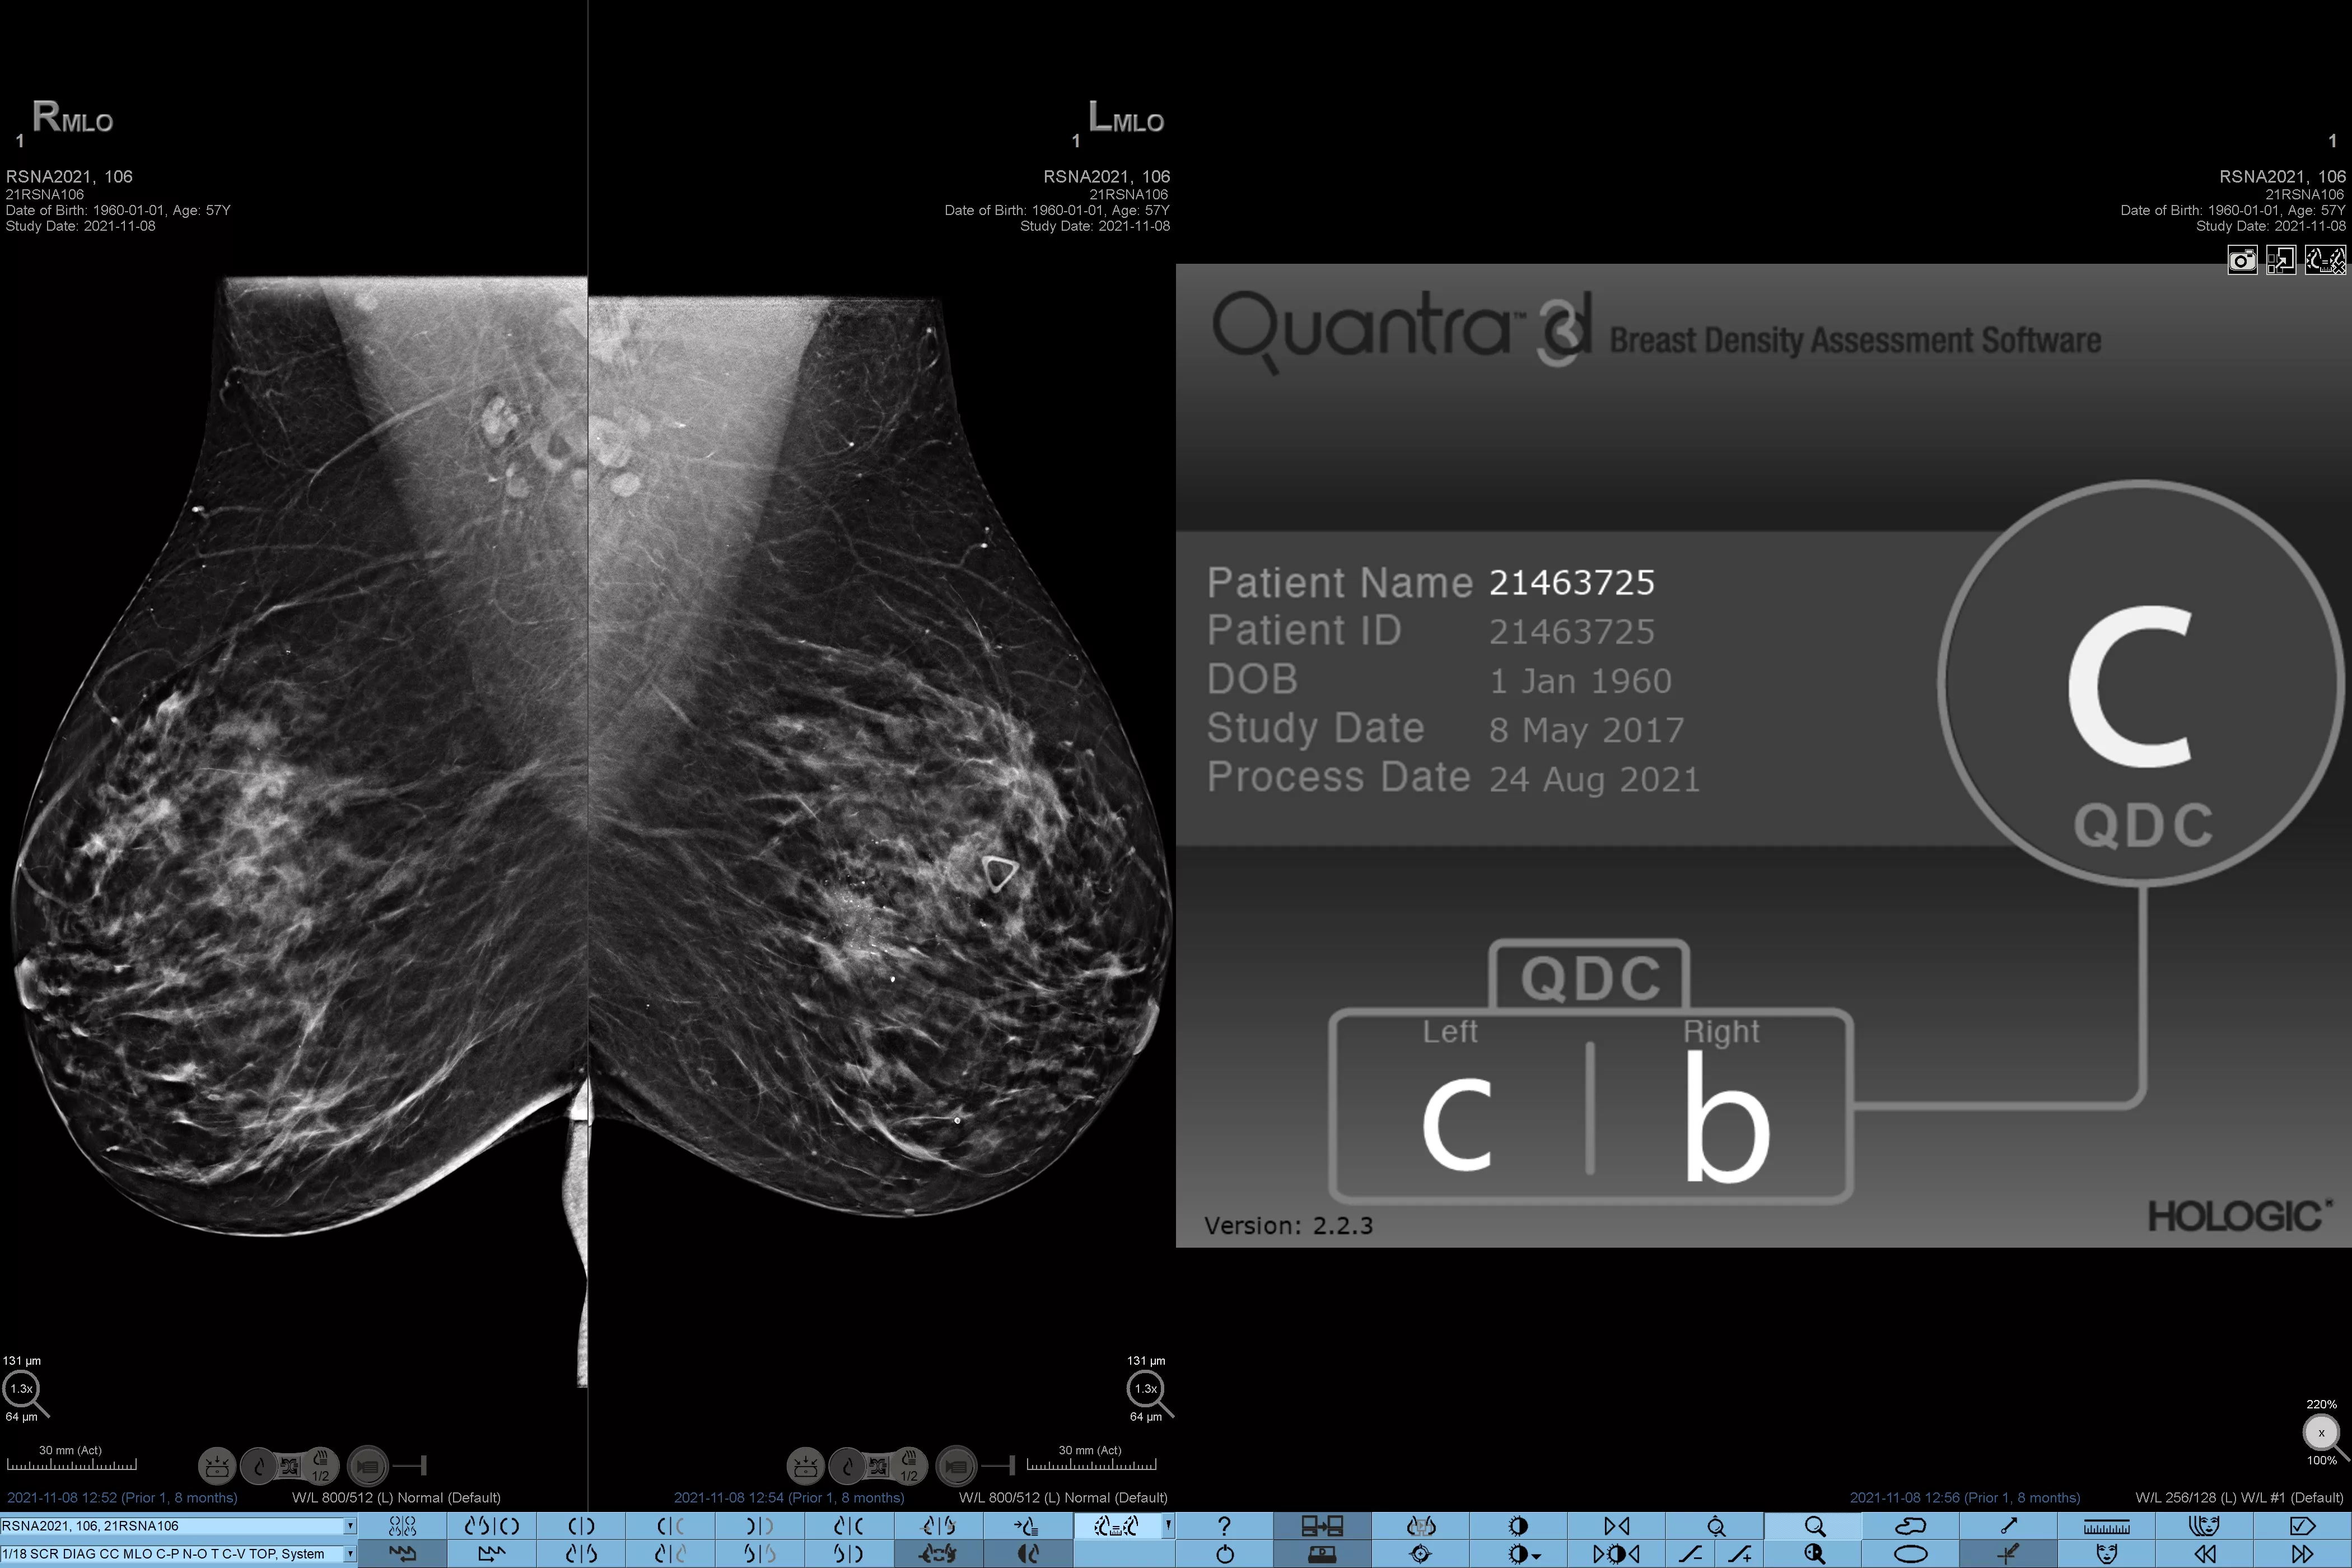

Higher breast density is known to increase a woman’s risk for breast cancer.1 The need for accurate, unbiased analysis is therefore critical. Powered by machine learning, Quantra technology software analyses both 2D™ and tomosynthesis images for distribution and texture of parenchymal tissue. It categorises breasts in four breast composition categories consistent with guidance from the American College of Radiology (ACR) BI-RADS Atlas 5th Edition.2

Objective machine learning algorithm that assigns breast density category based on analysis of breast tissue texture and patterns.

Quantra software’s unbiased algorithm analyse both 2D and tomosynthesis images to support your analysis by:

• Overcoming subjectivity in visual assessment, providing more consistent, and more reliable scoring.*

• Elevating the standard of care and standardises reporting.

*Scores are based on ACR BI-RADS categories, in line with the revised guidance by the American College of Radiation (ACR) BI-RADS Atlas 5th Edition. This accounts for pattern and texture, compared with volume, when determining density.